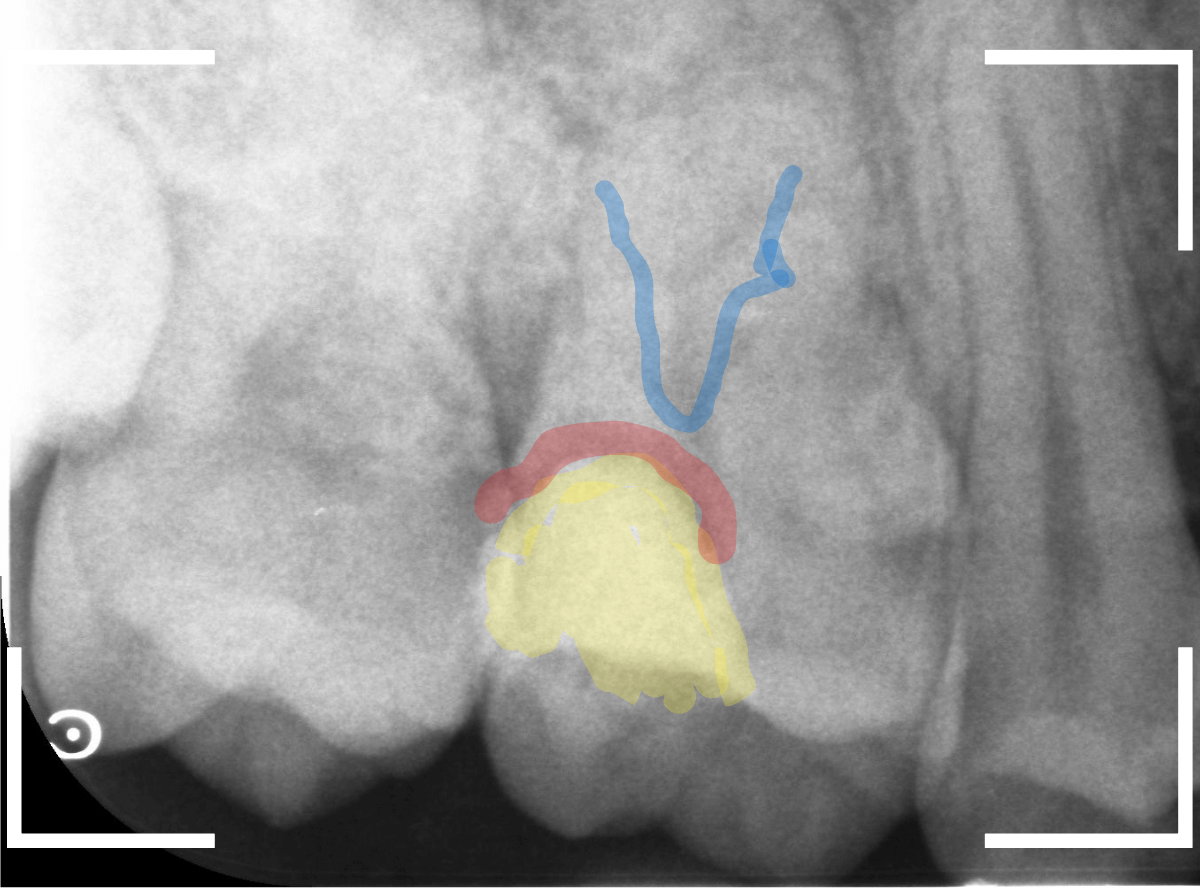

レントゲン写真で確認します。

青い線が歯の神経です。

赤い線が虫歯と思われる部分です。

思った通り、神経に達してしまいそうな大きな虫歯です。

患者さんには、神経を取る治療が必要な可能性が高い事を説明します。

レントゲン写真を撮影しました。

青い線が神経

黄色い線がレジン

赤い線が虫歯

です。

思ったよりも深い虫歯をレジンで埋めてあったようで、さらにその中が虫歯になっている状況です。

神経までかなり近い虫歯と思われます。